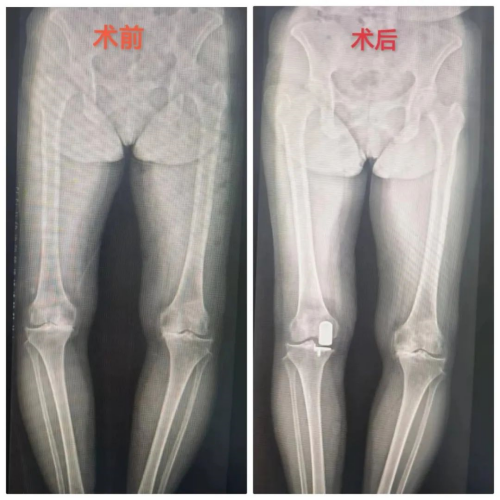

运动医疗关节骨病科主任李良军介绍:“膝关节作为人体结构最复杂的关节,又是负重关节,容易患上骨性关节炎,以往大多采用的是一刀切的全膝关节置换术,但实际上许多膝关节骨性关节炎患者只是单一间室局部病变,也就是只有一部分产生了病变。韧带结构良好,不需要全膝置换,单髁置换应运而生。所谓单髁置换,就是精准置换产生病变的部位,最大限度保留膝关节功能和本体感觉。单髁置换相比全膝置换有几大优势,主要体现在:切口小,出血量少,可以最大化地保留正常组织,术后恢复快,本体感觉好,最重要的是更具人性化。当然,如果是整个膝关节都出了问题,还是首选全膝关节置换了。”